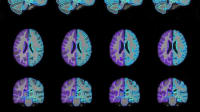

Bartron's Med-Seg unit incorporating NASA's HSEG technology provides improved diagnoses for a wide range of medical images, including computed tomography scans, positron emission tomography scans, magnetic resonance imaging, ultrasound, digitized X-ray, digitized mammography, dental X-ray, soft tissue analysis, and moving object analysis; the technology is also equipped to evaluate soft-tissue slides such as Pap smears. Using Med-Seg, physicians and health care practitioners can take any unmanipulated medical image and segment it to see features in the image that were not previously visible to the naked eye. The clinicians can additionally isolate one particular area of interest in an image to compare it with many other reference images databased at other health care facilities, for instance.

As an open workstation, the Med-Seg system is composed of a front-end terminal for segmentation feature extraction, pattern recognition, and classification of the medical images. These images can be transmitted to Med-Seg via satellite, cable, digital subscriber line, or dial-up (for smaller images).